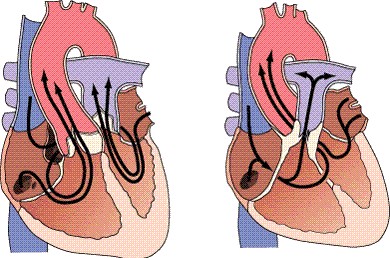

Transposición completa de las grandes arterias En esta lesión, la aorta se origina en el ventrículo derecho, a la derecha y delante de la arteria pulmonar, que se origina en el ventrículo izquierdo. Esto provoca la existencia de dos circulaciones separadas y paralelas, izquierda por lo que es indispensable que exista una comunicación entre ambas después del nacimiento para la supervivencia....

Transposición completa de las grandes arterias En esta lesión, la aorta se origina en el ventrículo derecho, a la derecha y delante de la arteria pulmonar, que se origina en el ventrículo izquierdo. Esto provoca la existencia de dos circulaciones separadas y paralelas, izquierda por lo que es indispensable que exista una comunicación entre ambas después del nacimiento para la supervivencia.... -